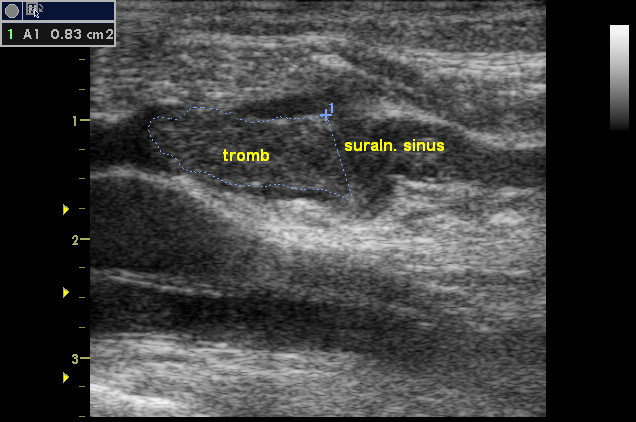

1. пациентка с не массивной ТЭЛА. Флотирующий тромб в медиальном суральном синусе, не досигающим уровня ПкВ 7 см. На момент осмотра второй эпизод ТЭЛА (первый перенесла дома). Погибла на 3-й день

Вложения:

Image0176.jpg

Image0176.jpg [ 88.17 | Просмотров: 33448 ]